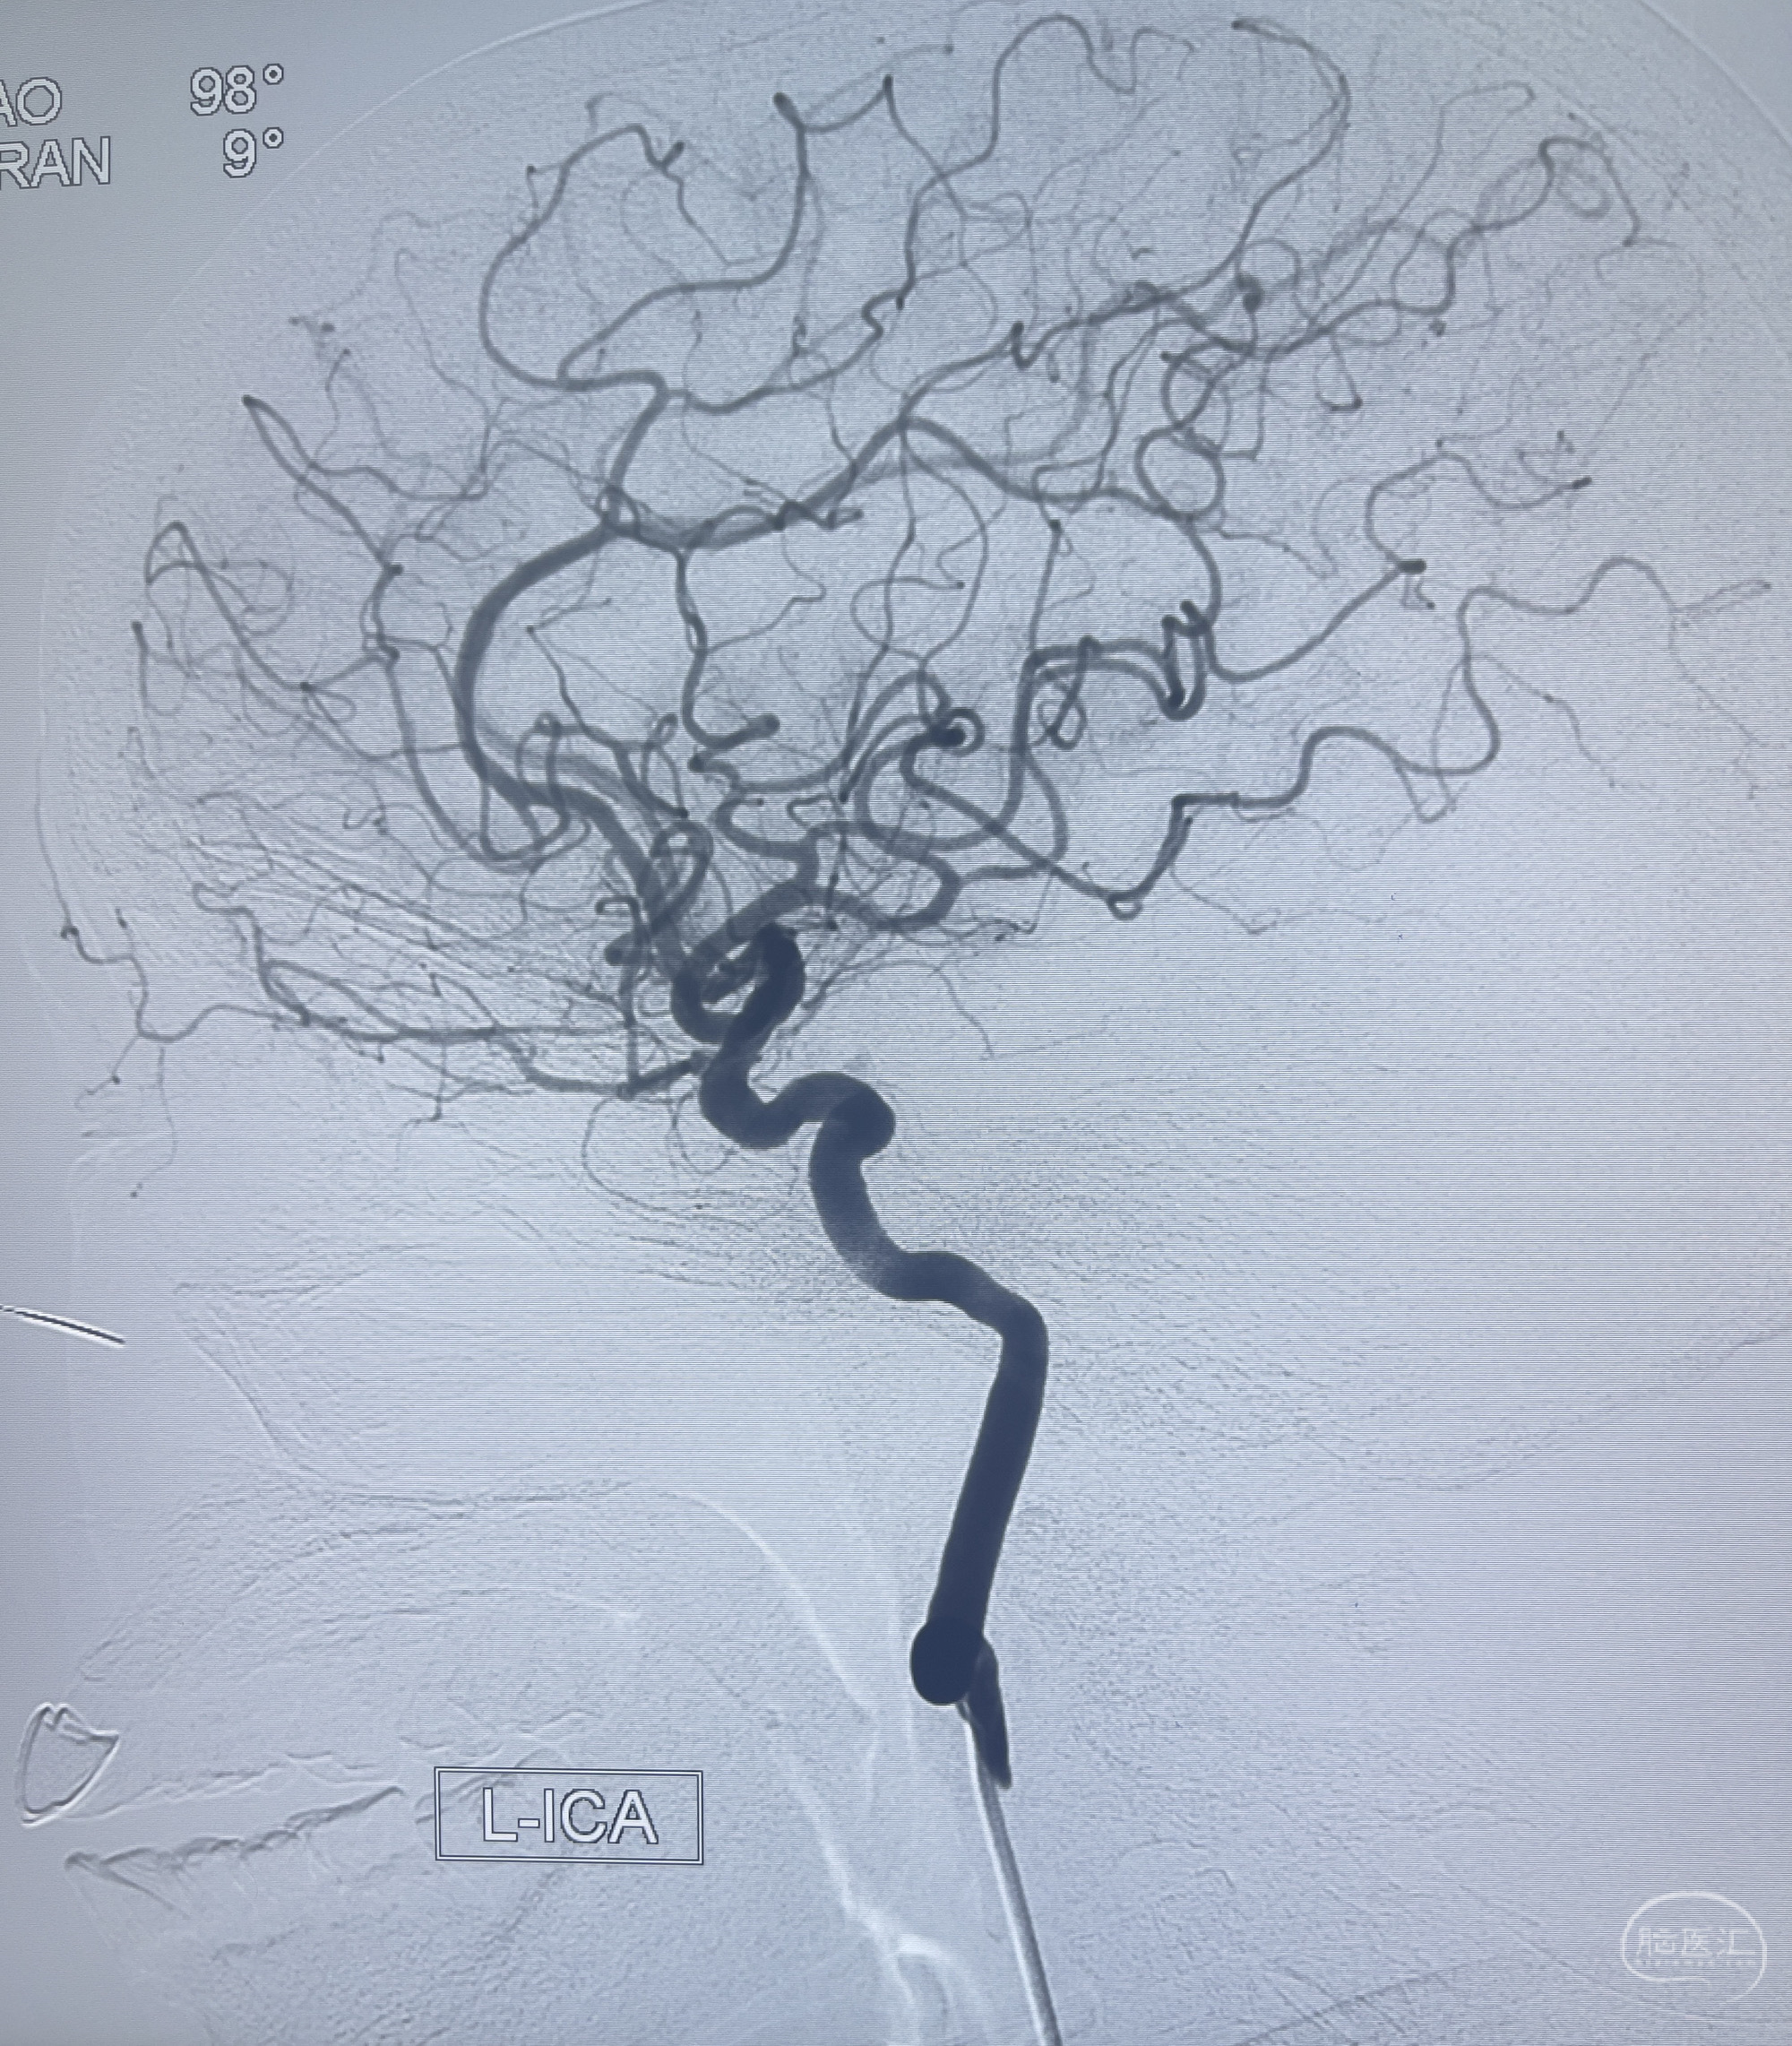

202.04.28脑血管造影:右侧大脑后动脉远段闭塞,右侧椎动脉V4段可见“囊状造影剂填充影”,大小7.64*7.65mm,可见PICA由动脉瘤发出;